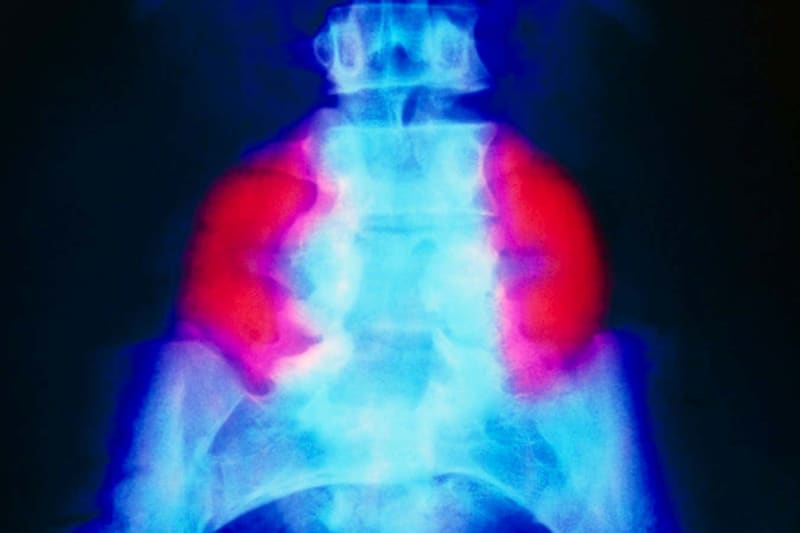

Spina bifida affects roughly 1 in 2,800 babies in the US each year when their spine and spinal cord don't fully develop in the womb. In the most severe form, the spinal cord pushes through a gap in the vertebrae, often preventing children from walking and causing lifelong bladder and bowel problems.

Scientists at the University of California, Davis wondered if adding stem cells could help repair spinal tissue more completely. They created a patch made from stem cells harvested from donated placentas, embedded in a matrix of proteins that help cells grow.

Six pregnant women carrying babies with spina bifida agreed to try the experimental treatment. Surgeons performed the standard repair surgery, then placed the stem cell patch over the spine before sewing the skin around it.

The results exceeded expectations. Brain scans showed the patch completely reversed a dangerous complication where fluid buildup pushes the brain through the base of the skull. All six babies healed perfectly at birth with no abnormal cell growth, a key safety concern when using stem cells in developing fetuses.